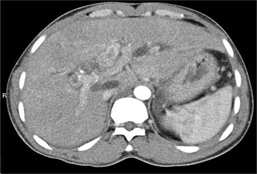

Al segundo día después de la admisión, se complementó estudio con tomografía axial computarizada previa administración de contraste EV (Fig. 3) y se observó: vesícula biliar distendida, colédoco dilatado con litiasis mixta cálcica-biliar, alargada de 13x7mm en su interior y calcificaciones mixtas cálcica-biliares alargadas dentro de los conductos biliares intrahepáticos, los cuales lucían dilatados. En la (fig. 4) se comprobó: páncreas de tamaño normal, con mínima cantidad de líquido y edema peri pancreático, confirmando el diagnóstico de colecistitis litiásica y pancreatitis aguda secundaria, dilatación y litiasis de vías biliares intra y extrahepáticas.

Otras características que pueden detectarse mediante ecografía incluyen cálculos biliares, abscesos hepáticos, "biloma" y colangiocarcinoma. Se puede realizar una aspiración percutánea con aguja fina guiada por ecografía en caso de sospecha de tumor hepático. 11,12 En este caso, la primera investigación por imágenes realizada fue la ecografía de abdomen que muestra un cálculo alargado dentro del colédoco dilatado e imagen ecogénica dentro de las vías biliares intrahepáticas dilatadas y engrosamiento ecogénico adyacente a la pared de la vía biliar. Posteriormente se realizó una tomografía computarizada de abdomen con contraste, para definir la dilatación de la vía biliar que se aprecia mejor en un estudio contrastado, la constitución mixta de las litiasis, propias de los cálculos biliares y sirvió además para descartar otras complicaciones como formación de abscesos, cirrosis hepática, biloma o rotura de la vía biliar con peritonitis y colangiocarcinoma, como vimos la pancreatitis estaba presente como complicación. No se realizó colangiopancreato resonancia a este paciente porque fue remitido a institución terciaria para definir diagnostico y tratamiento, donde fue diagnosticado finalmente con la CPR por los hallazgos de litiasis biliares, estenosis fibrótica y dilatación de las vías biliares.